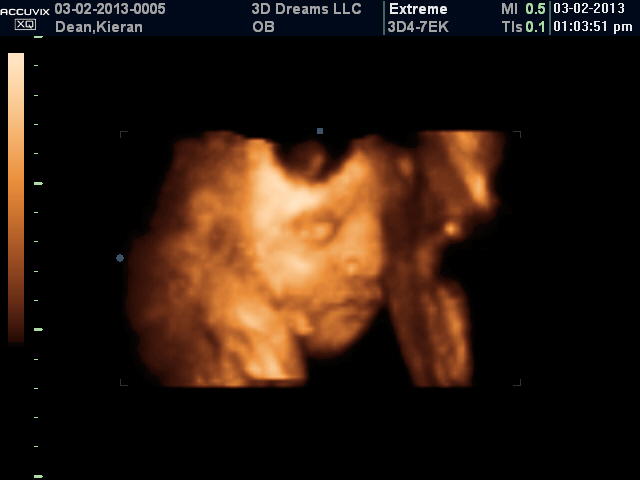

3-D Ultrasound at 31 weeks 4 days

This was my favorite shot from the whole ultrasound...it shows her budgy nose and plump little lips!

Once again, she had her hands all up in her face the entire time!